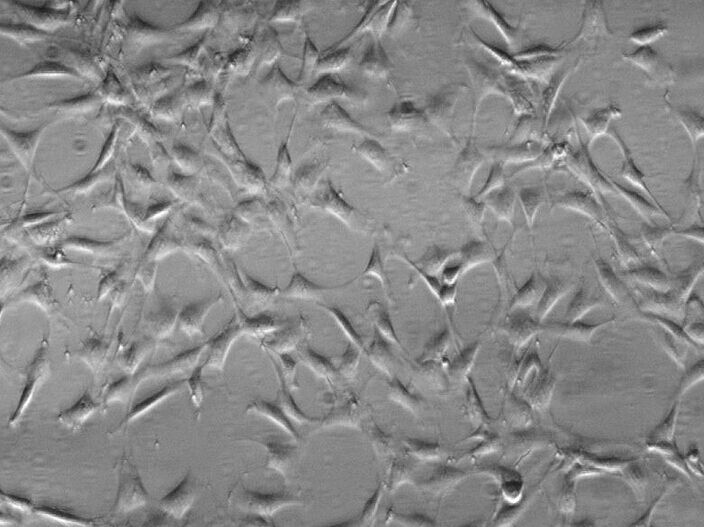

细胞形态:贴壁

细胞活力:95%(Viability by Trypan Blue Exclusion)

培养条件:RPMI-1640 +10% FBS;37℃,5% CO2

5、 2-5分钟后,轻轻震荡培养皿。使HPMEC 人肺微血管内皮细胞从瓶壁脱离形成细胞悬液。显微镜下观察若细胞由贴壁变为悬浮就加入血清(即原培养液)终止消化。